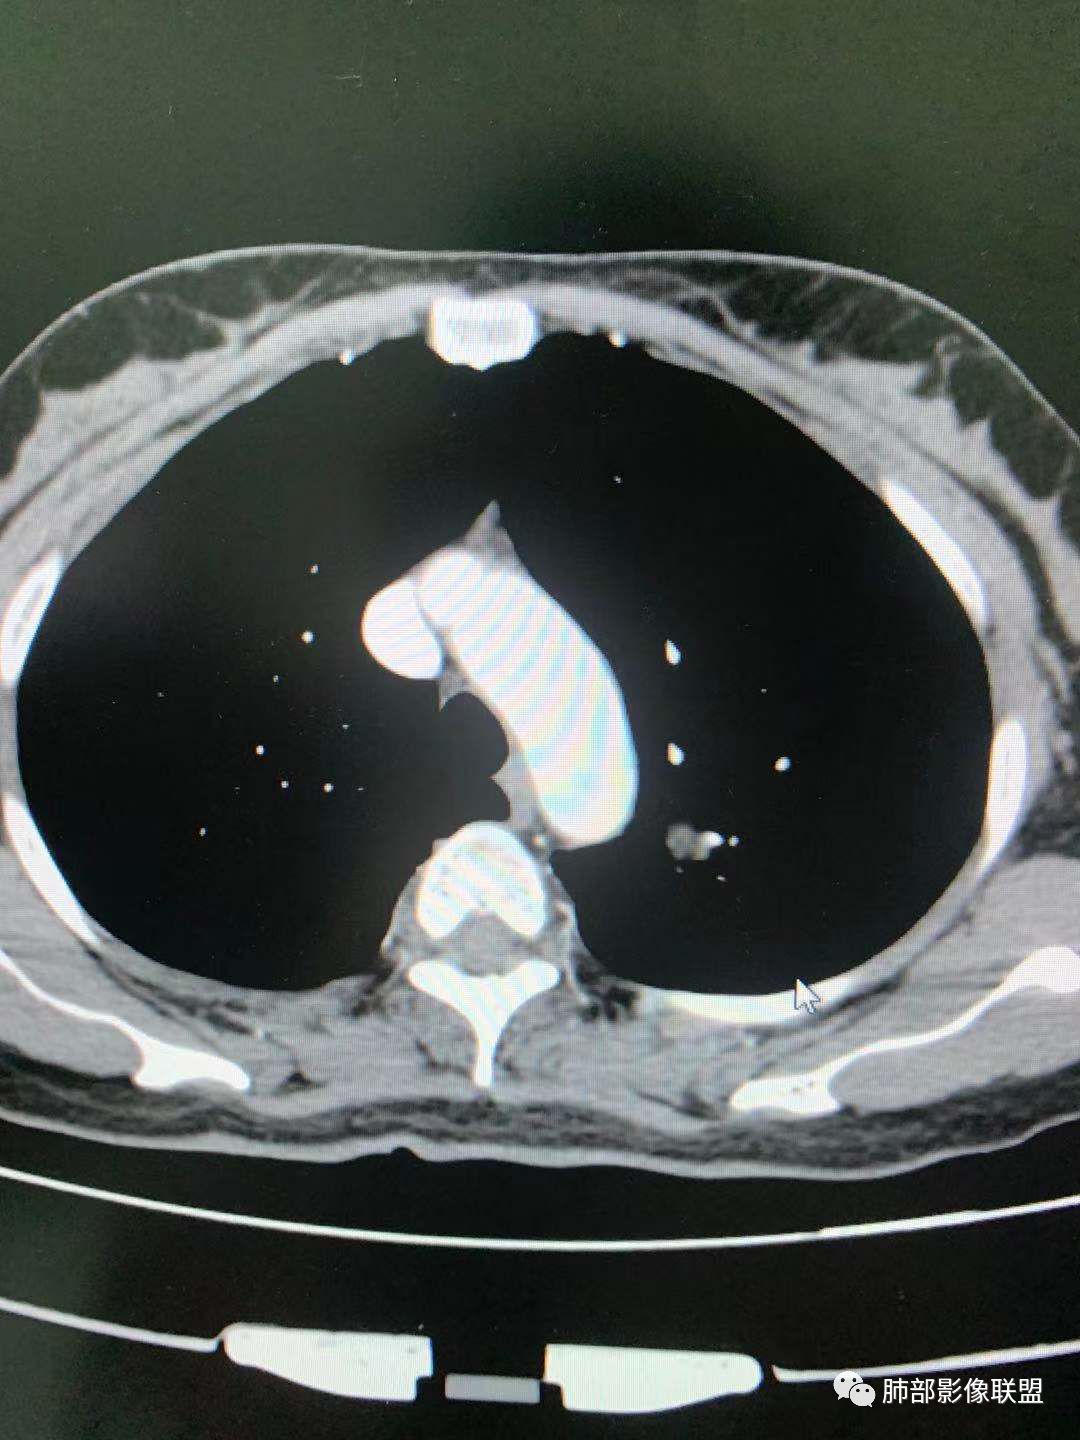

CT值30HU;增强后:41/76HU

强化幅度:46HU

边缘平直,延迟强化,血管贴边,支气管推移,毛刺较软,收缩力较弱。

一.尖后段高密度大结节:

1.左肺上叶尖后段较大类圆形实性密度结节影,密度均匀,中等程度强化。

2.实性密度区边缘相当清楚,表面欠光整,偶见毛刺、棘突和旁出血管结构,未见典型的深分叶及邻近胸膜凹陷。

3.可疑支气管进入受阻。可惜缺乏连贯图像或冠矢状位以资判断。

4.病灶与胸膜之间有连线,邻近段支气管及肺血管整体后移,提示病灶还是有一定收缩性。

如上,单就这实性结节,硬化性肺细胞瘤(PSP)和腺癌似乎都能够解释,形态太规整了一些。

5.病灶周围见边界清楚的磨玻璃影,有点醒目,有点意外!

这是无论如何不能忽视的征象!

这点强烈提示,要么整个病灶恶性(腺癌),要么良性病灶旁滋生恶性病灶。